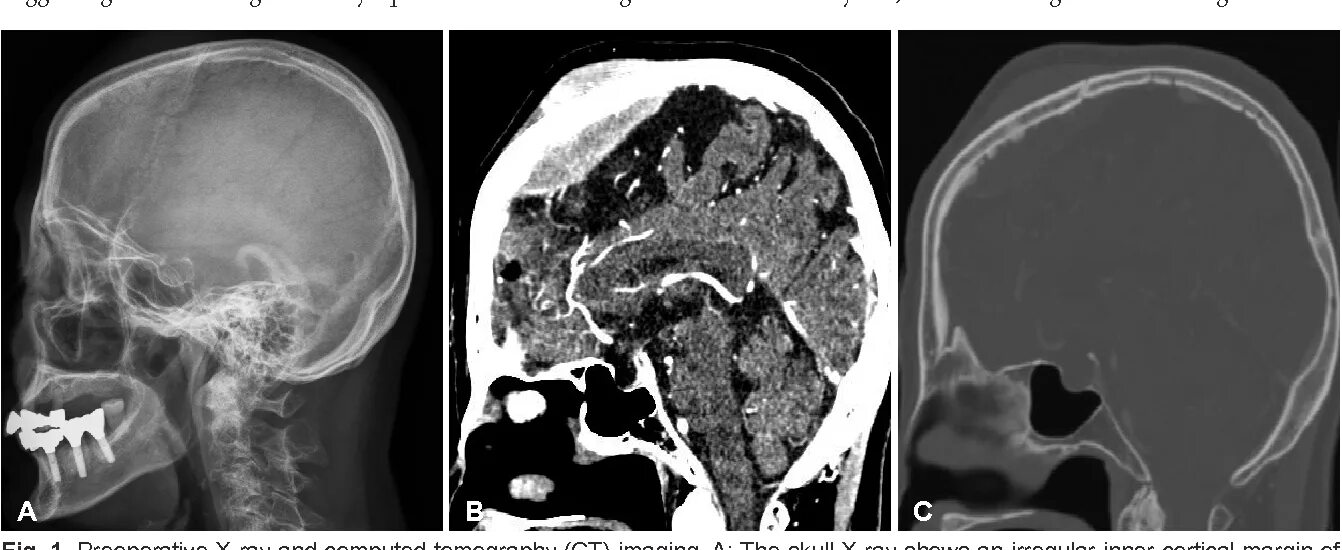

Остеома мрт